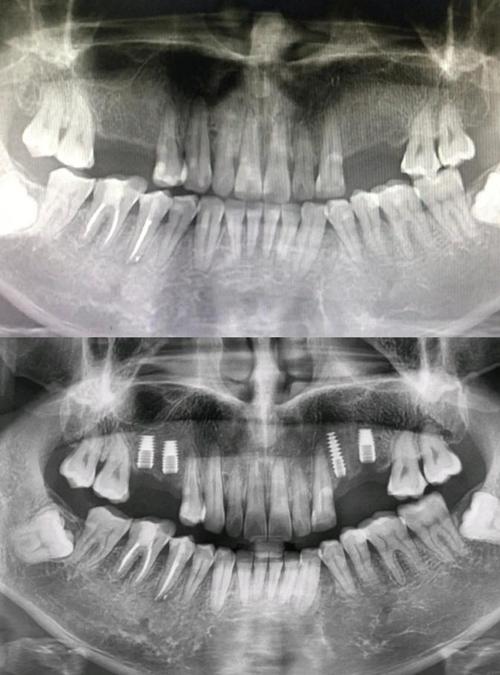

牙槽骨的骨高度、宽度、密度是决定能否植牙及选择何种种植体的核心指标,传统X光片(如根尖片、曲面断层片)是二维影像,存在放大失真、重叠干扰等问题,无法准确测量骨量,下颌骨后区的牙槽骨可能因吸收呈现“倒凹”形态,二维片容易误判骨量充足,实际三维CT才能清晰显示骨缺损区域,避免种植体穿出骨壁。

识别重要解剖结构,规避手术风险

口腔内分布着密集的神经、血管,如下颌的“下牙槽神经管”(内有神经血管束,损伤会导致下唇麻木)、上颌的“上颌窦”(底部与后牙区牙槽骨相邻,穿刺可能引发感染),CT能精准定位这些结构的走行、位置及与牙槽骨的距离,当后牙区骨高度不足5mm时,CT可明确上颌窦底的位置,判断是否需要“上颌窦内提升”或“外提升”手术,避免盲目操作导致上颌窦穿孔。

制定个性化手术方案,提升成功率

通过CT三维重建,医生可在术前模拟种植体植入的路径、角度、深度,选择最适合的种植体型号(如短种植体、窄直径种植体),对于骨量严重不足的患者,CT能明确植骨的范围和量(如自体骨、骨粉填充量),避免术中临时调整方案,数据显示,术前CT引导的植牙手术,成功率比单纯依靠经验提升15%-20%,尤其适用于全口种植、即刻种植等复杂病例。

CT不仅能评估术前骨条件,还能在术后通过对比种植体周围骨的密度变化,判断骨结合情况(即种植体与骨组织融合程度),若发现骨吸收异常,可及时干预,避免种植体松动脱落。